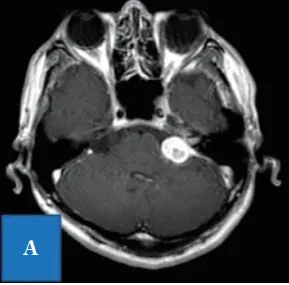

听神经瘤作为桥小脑角区最为常见的肿瘤,临床表现多样,比如听力下降、耳鸣、头痛、平衡失调,面部疼痛和麻木,这类肿瘤多见于30岁至60岁人群,很少见于年轻患者。 本期要分享的病例是...